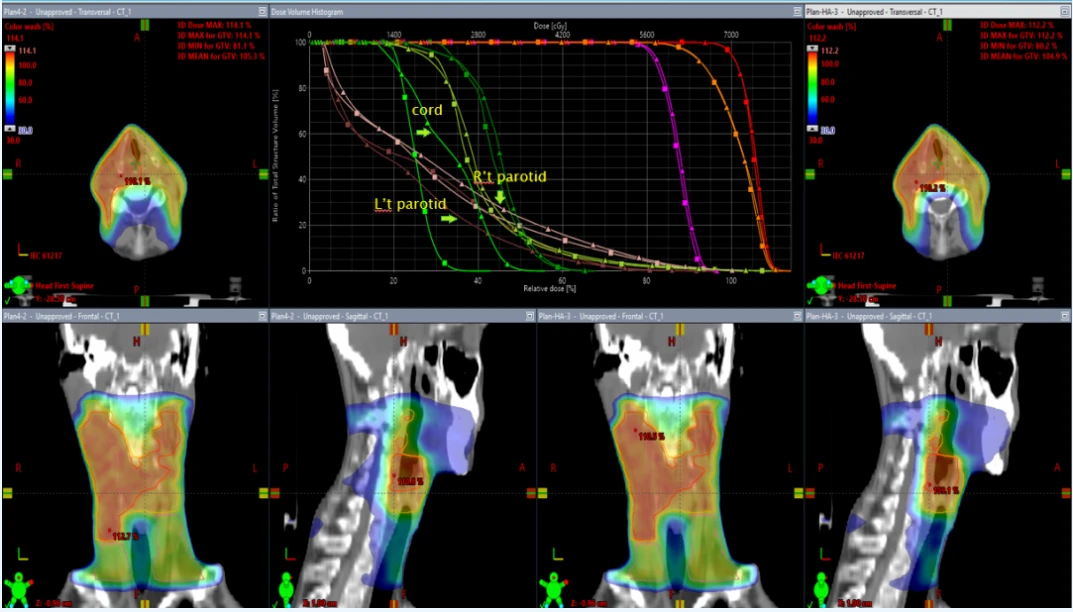

比较Halcyon 2个弧与Halcyon 3个弧,如下图:

▲HAL 2个弧 ■HAL 3个弧

HAL 3arcs的Cord、R’t parotid的整体剂量较低